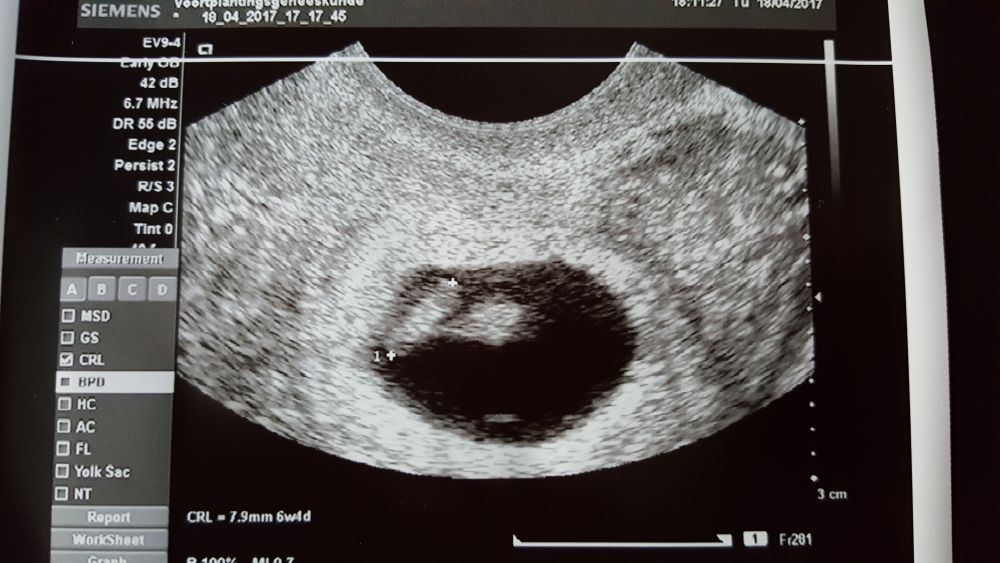

Het verlies van een kindje in de prille zwangerschap is ingrijpend. Je rouwt niet alleen om het leven dat is gestopt, maar ook om alles wat er nooit zal zijn. Geen echo met kloppend hartje. Geen geboortekaartje. Geen eerste huiltje. En toch was je kindje gewenst. En jij bent ouder. Ook al ziet niet iedereen dat.

echo prille zwangerschap _ eerste trimester -